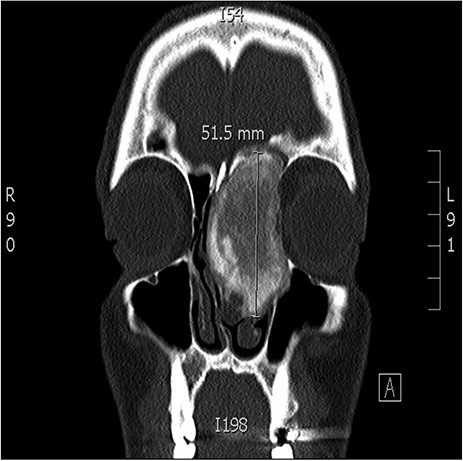

A 34-years-old man presented with left-sided facial pain, headache and nasal obstruction for a long duration, with no history of bleeding per nose, nor blurring of vision. Upon examination, there was a large left nasal cavity bony outgrowth pushing the middle turbinate and pushing the nasal septum to the right side (Fig. 1). CT scan of the paranasal sinuses showed a large mass centered in the left anterior ethmoid sinus, the mass measures 3.7 × 2.9 cm (trans-axial) (Fig. 2) and 3.7 × 5.2 cm (coronal) (Fig. 3), it has a heterogeneous density with calcified and soft-tissue component. The calcified component is in the periphery with central soft tissue density. The mass resulted in remodeling of adjacent bones with nasal septal deviation to the right, it extended superiorly to involve the frontal sinuses as well as invading the left cribriform plate and intracranial extension (Fig. 4), it extended inferiorly displacing the medial wall of the left maxillary antrum. The medial aspect of the mass caused remodeling of the medial wall of the left orbital cavity with bulging and displacement of the medial rectus muscle. The mass resulted in obstruction of the left frontal sinus.

Coronal CT image of the sinuses showing a mass encroaching the orbit and skull base.